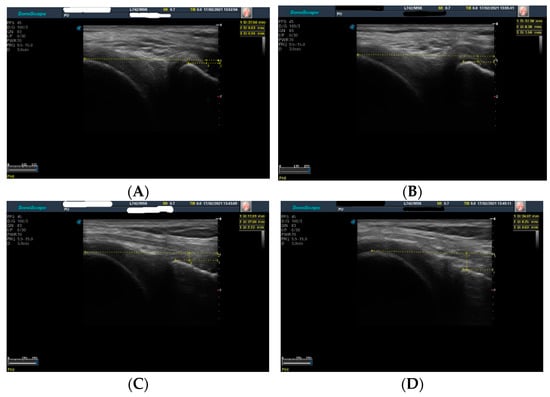

Dynamic Ultrasound Assessment of the Anterior Tibial Translation for Anterior Cruciate Ligament Tears Diagnostic

2.2. Assessments